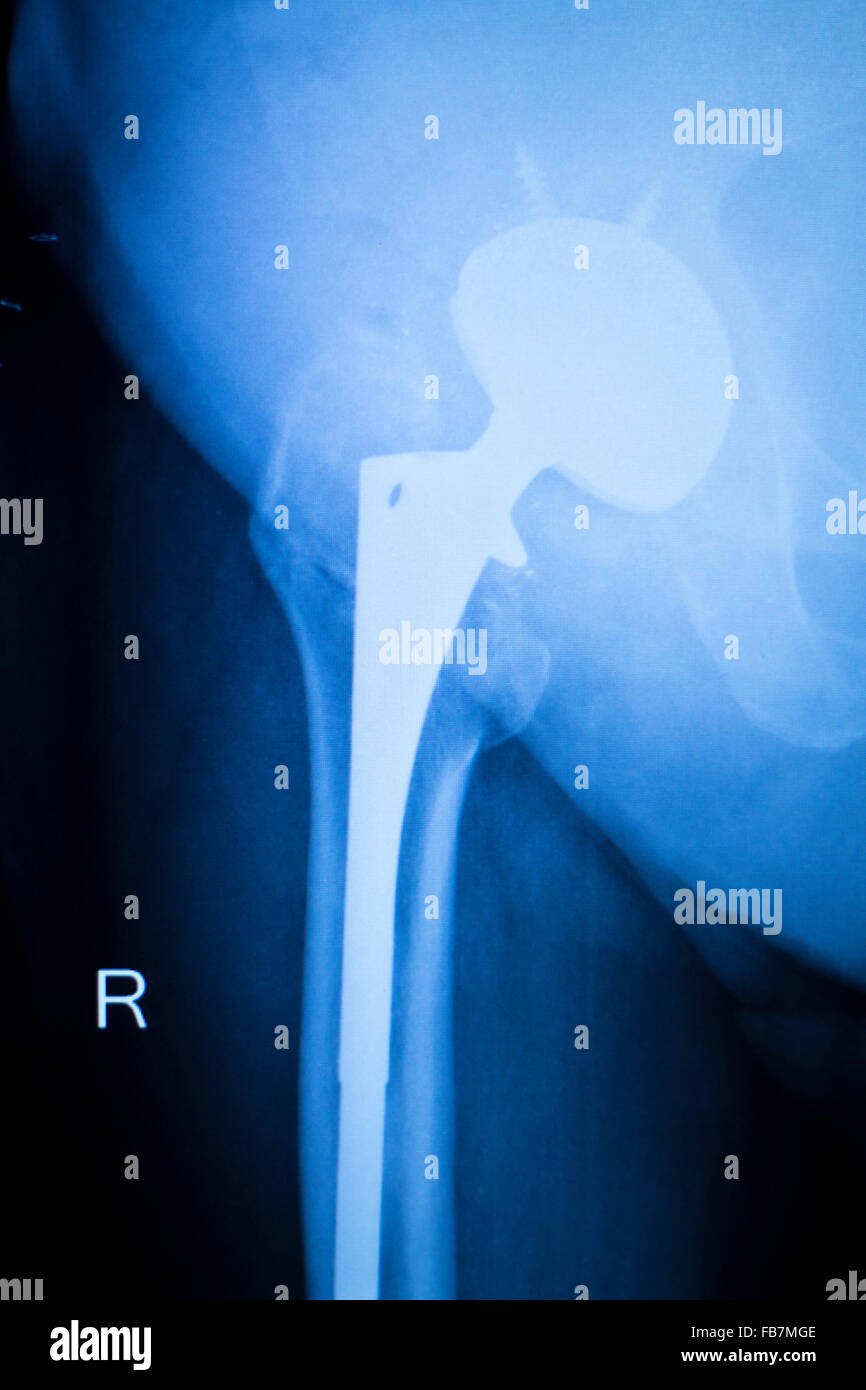

Hip joint replacement xray showing ball and socket joint's titanium Titanium Hip Replacement Problems If your hip implant has been causing pain or other problems, it might be because it’s made of all metal components. Symptoms of a loose hip replacement include pain in the groin or upper. This can be caused by the shaft of the. You’ve recently had a hip replacement and you have: For most people who undergo the surgery, hip. Titanium Hip Replacement Problems.

From journals.lww.com